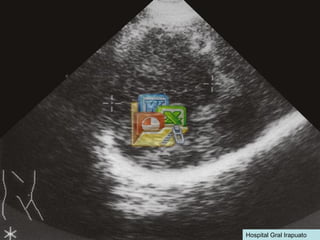

RECAPITULEMOS 1- DIAGNÓSTICOS HASTA AHORA. 2- POSIBILIDADES PARA LA IMAGEN ÚLTRASONOGRÁFICA. 3- MEDIOS PARA CONFIRMAR O DESCARTAR ESAS POSIBILIDADES. 4- TRATAMIENTO INICIAL.

PARACLINICOS ULTRASONIDO: vesícula biliar con lesiones cálcicas menores de 8 mm, hígado de menor tamaño, contorno irregular hiperecogénico y presencia de lesión en lobulo izquierdo hipoecogénica heterogenea de 8.7 por 3.7 , vena porta de 20 mm, bazo de 14 por 6 cm, ascitis. ALFA FETO PROTEINA: 517 ¿SIGUIENTE PASO?

RECAPITULEMOS 1- DIAGNÓSTICOSHASTA AHORA. 2- POSIBILIDADES PARA LA IMAGEN ÚLTRASONOGRÁFICA. 3- MEDIOS PARA CONFIRMAR O DESCARTAR ESAS POSIBILIDADES. 4- TRATAMIENTO INICIAL.

PARACLINICOS ULTRASONIDO: vesículabiliar con lesiones cálcicas menores de 8 mm, hígado de menor tamaño, contorno irregular hiperecogénico y presencia de lesión en lobulo izquierdo hipoecogénica heterogenea de 8.7 por 3.7 , vena porta de 20 mm, bazo de 14 por 6 cm, ascitis. ALFA FETO PROTEINA: 517 ¿SIGUIENTE PASO?